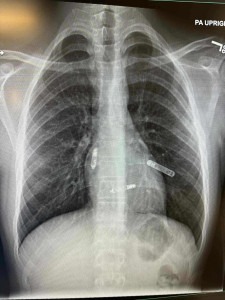

Prije nekoliko dana je u američkoj saveznoj državi Floridi izvedena revolucionarna kardiohirurška intervencija koja će ući u medicinsku historiju. Naša Mostarka, dr. Svjetlana Tišma-Dupanović, kardiologinja i pedijatrica, uspješno je pacijentu ugradila dvokomorni pejsmejker direktno u srčane šupljine — u pretkomoru i komoru — koji sinhronizovano stimulišu pravilan rad srca.

Ovo je prva takva operacija izvedena na Floridi, a ujedno predstavlja veliki napredak u liječenju bolesti srca, posebno za pacijente sa poremećajima srčanog ritma i slabijom pumpnom funkcijom srca.

Tradicionalni pejsmejkeri postavljaju se ispod kože grudnog koša, a žice prolaze kroz vene do srca. Nova tehnologija, koju je primijenila dr. Tišma-Dupanović, omogućava direktnu ugradnju uređaja unutar srca — bez žica koje prolaze kroz krvne sudove. Ovaj dvokomorni (biventričularni) pejsmejker sinhronizuje rad pretkomora i komora, čime se postiže pravilniji ritam i veća efikasnost pumpanja krvi.

U medicinskoj terminologiji, ovakav zahvat spada u “srčanu resinkronizacijsku terapiju” (Cardiac Resynchronization Therapy – CRT), koja koristi više stimulacijskih tačaka za postizanje optimalne kontrakcije srčanog mišića.